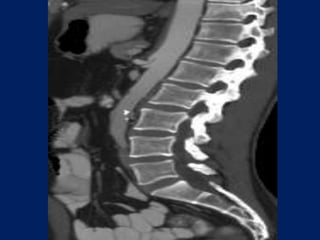

angulations and narrowing of the proximal celiac axis. Sagittal 3D image of a patient with epigastric pain

angulations and narrowingof the proximal celiac axis. Sagittal 3D image of a patient with epigastric pain

Sagittal (MIP) of a patient with recurrent abdominal pain reveals focal calcified plaque.

Sagittal (MIP) ofa patient with recurrent abdominal pain reveals focal calcified plaque.